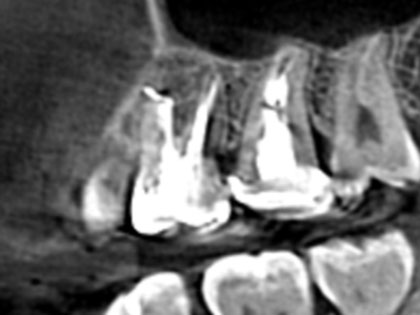

• 術前の写真がこちら

• 歯根端切除の術前1

• 歯根端切除の術前2